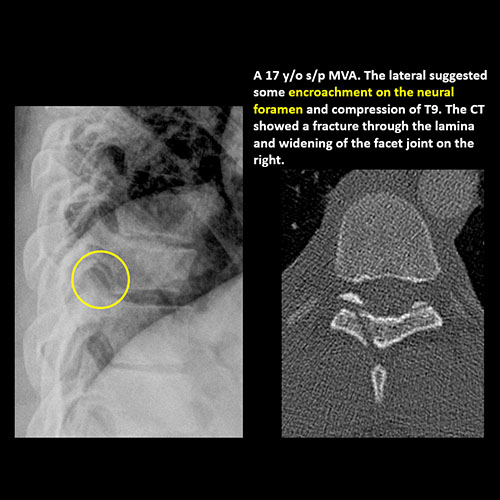

There is narrowing or encroachment of a neural foramen other than from degenerative change. [Yes/No]

There is anterior wedging and/or compression of a vertebral body. [Yes/No]

There is widening, rotational abnormality, or displacement of facets at any motion segment. [Yes/No]